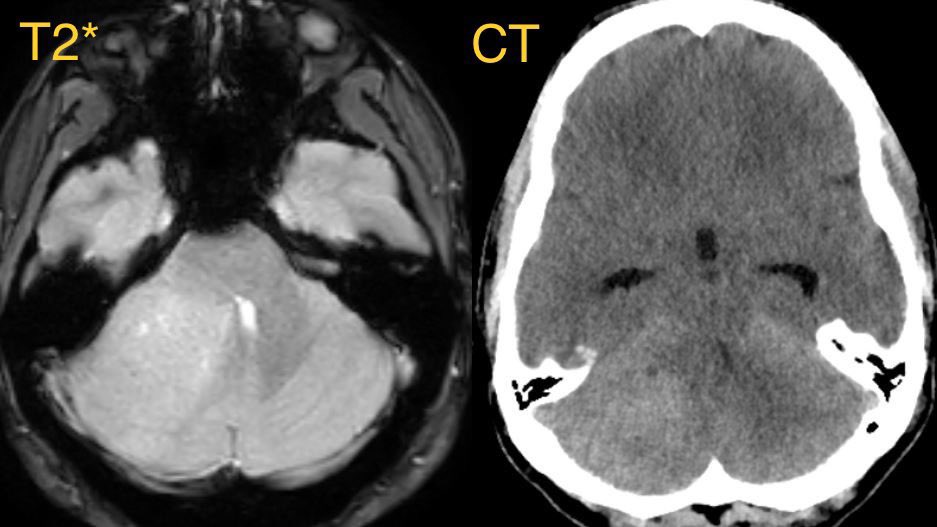

🔷Imaging:

💡 Hypercellular tumor so DENSE on CT and DIFFUSION RESTRICTION (consistent feature)

▶️Round/lobulated morphology

▶️Hemorrhage is rare but calcifications seen in ~20%

💡 Most medulloblastomas enhance except group 4 which may have minimal to no enhancement

⭐️ Companion case of Lhermitte-Duclos - Unilateral cerebellar mass w/ striations due to hyperintense expanded fovea on T2 w/ normal signal intervening parenchyma

Typically there is no to little enhancement and high signal on DWI due to T2 shine-through w/ high signal on ADC x.com

💡 Both Lhermitte-Duclos & Medulloblastoma SHH can have a striated appearance! Use DWI/ADC, density on CT, & enhancement to distinguish!